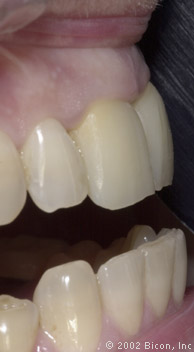

Плотный контакт «металл – металл» абатмента и стенок имплантанта обеспечивает надежную фиксацию и бактериальную непроницаемость соединения

Окончательный результат. Превосходная эстетика!